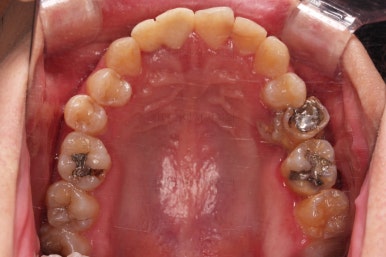

초진 시 입안의 모습입니다.

화살표는 결손 부위, 동그라기믄 유치잔존과 매복치아 부위입니다.

동그라미는 유치가 있는 상황이었는데요. 잇몸도 많이 파괴되어 있었고, 유치 자체의 상태도 좋지 못했어요.

동그라미 부분은 상한 유치가 보이는데, 그 하방으로 영구치가 매복되어 올라오지 못하고 있는 상태였어요.